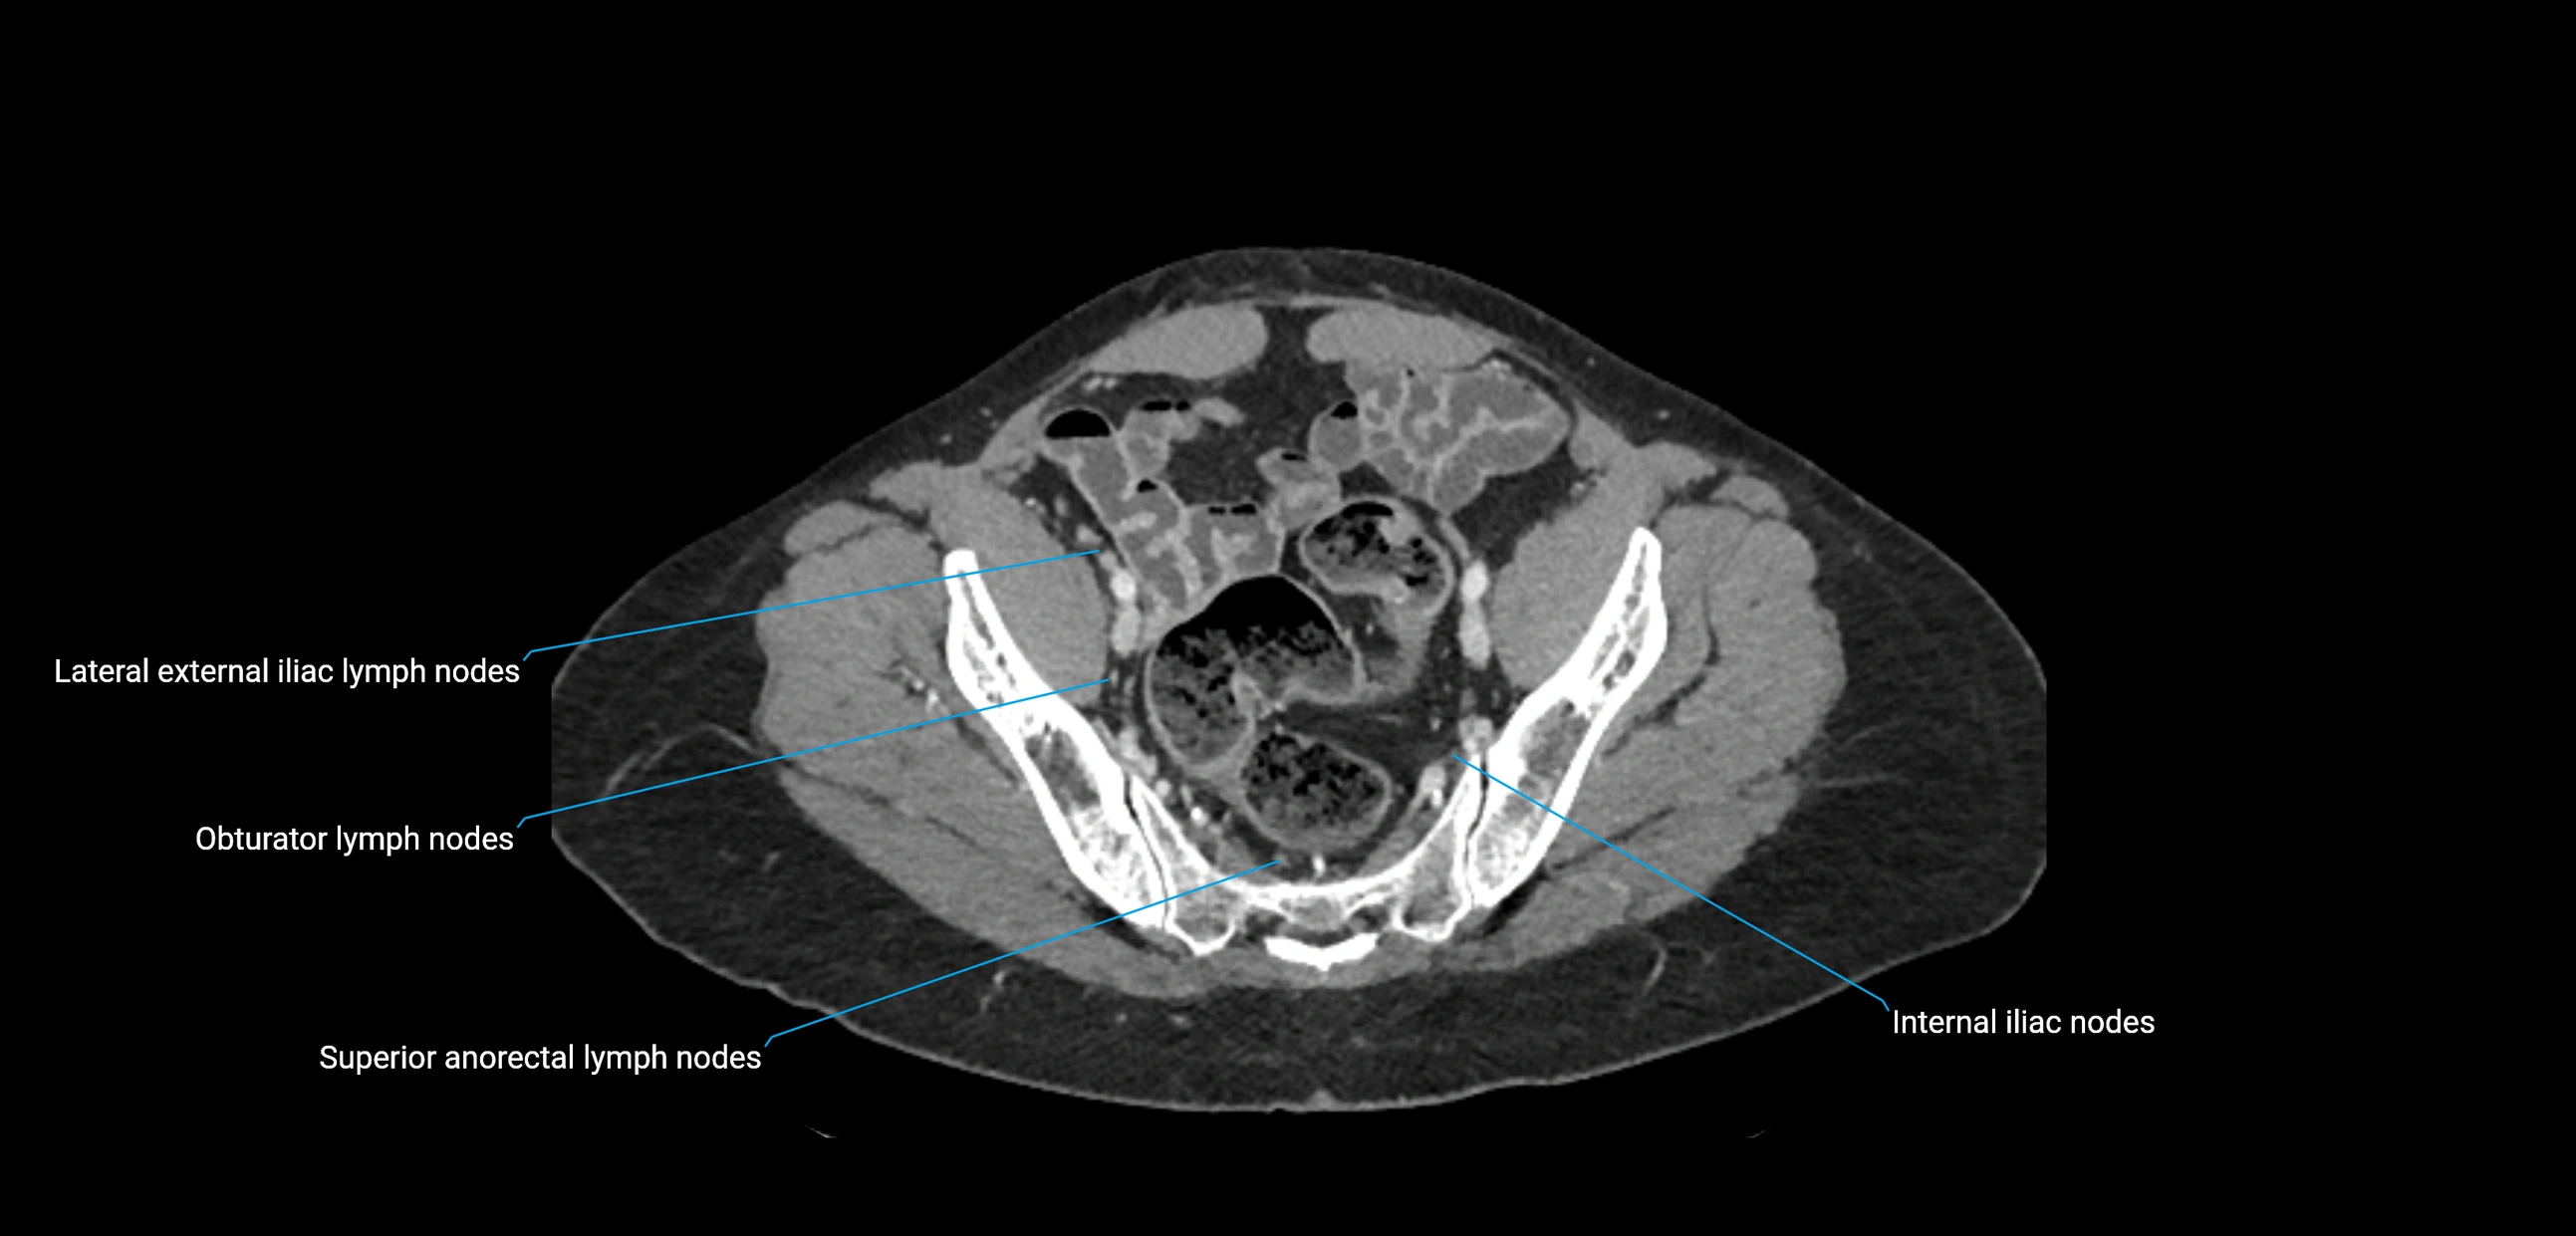

CT image

image